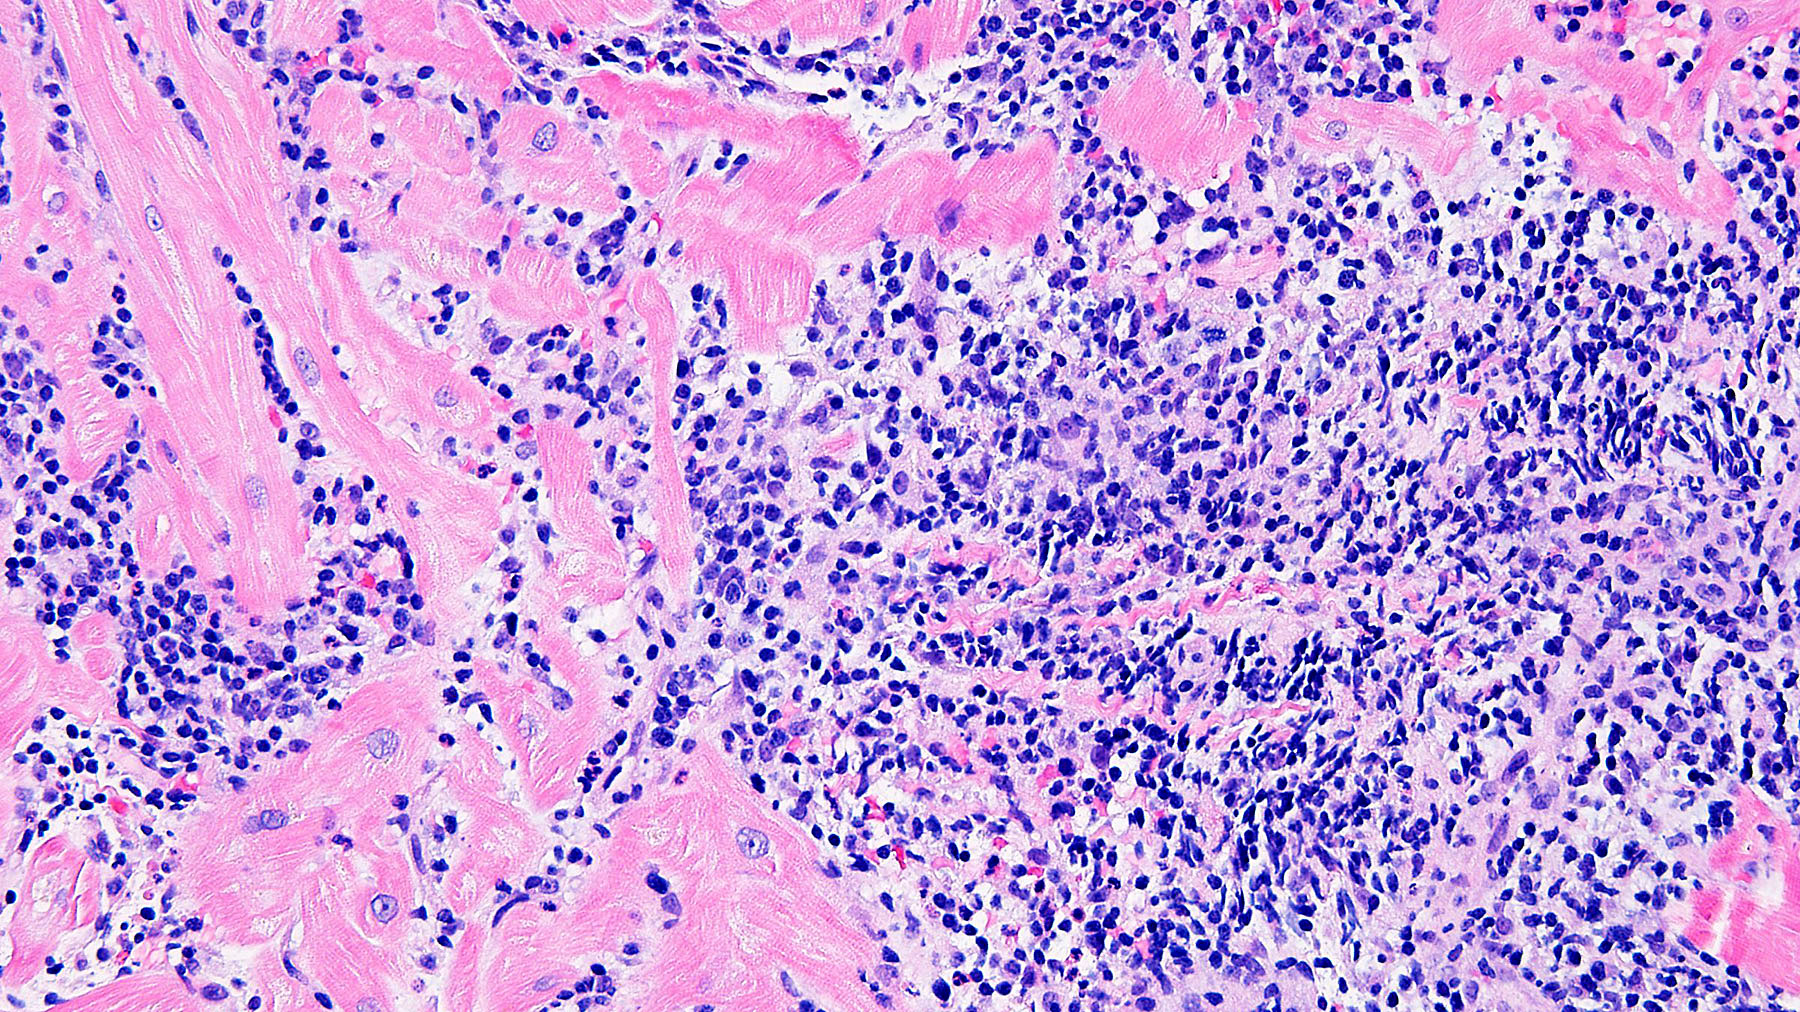

Figure E.  H&E x20

Histology: Biopsy of the myocardial tissue performed at one month after the transplant showed myocardial tissue with diffuse and severe polymorphous mononuclear infiltrates with extensive myocyte damage, interstitial edema, vasculitis and focal necrosis (H&E staining in Figures A, C & E, and corresponding trichrome stains in Figures B, D & F). Special immunohistochemistry (IHC) stain for CD4 in a consecutive section from E and F (Figure G) shows a predominant infiltrate for helper cells.  All these features are consistent with severe acute cellular rejection, ISHLT 2004 Grade 3R (ISHLT 1990 Grade 3B).